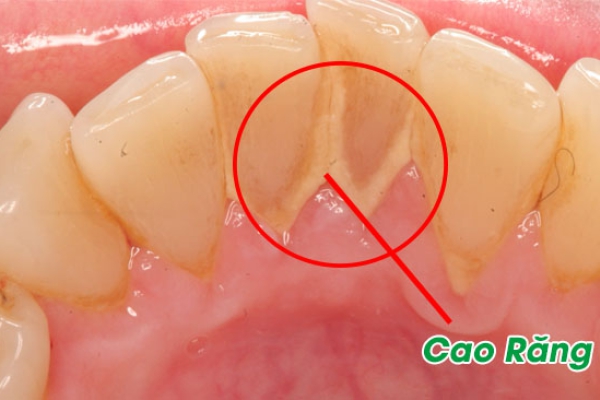

Cao răng, hay còn gọi là vôi răng, là mảng bám đã bị vôi hóa bởi các khoáng chất trong nước bọt, hình thành dưới và trên đường viền nướu.

Vi khuẩn luôn tồn tại trong miệng, ngay cả khi đã vệ sinh răng miệng. Chúng kết hợp với protein và thức ăn thừa, tạo thành mảng bám răng. Mảng bám này phủ lên răng và sau một thời gian sẽ cứng lại, trở thành cao răng, không thể loại bỏ bằng cách chải răng thông thường.

Cao răng chứa nhiều vi khuẩn, làm hỏng men răng và khiến nướu thô ráp, xốp, có thể tụt khỏi răng. Cao răng chỉ có thể được loại bỏ bằng các biện pháp vệ sinh răng miệng chuyên nghiệp. Nếu không được làm sạch, cao răng sẽ gây các bệnh về nướu, bao gồm viêm nha chu nguy hiểm.

Cao răng thường

Cao răng thường xuất hiện ở cổ răng, có màu trắng đục hoặc vàng nhạt. Với người hay hút thuốc lá, cao răng sẽ có màu sẫm hơn. Vôi răng thường gây viêm nướu, nếu không điều trị kịp thời sẽ gây chảy máu chân răng, máu ngấm vào lớp cao răng và chuyển thành cao răng huyết thanh.